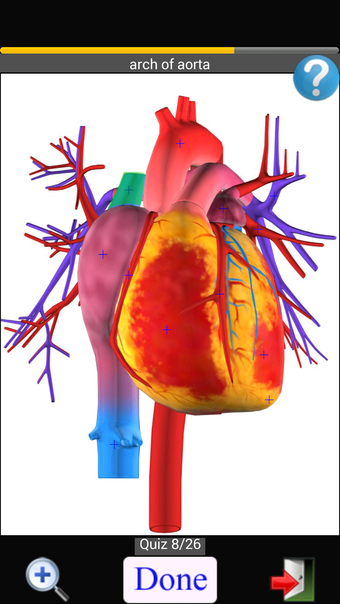

Anatomy Quiz Free es una aplicación de Android de Education Mobile que ofrece una amplia gama de cuestionarios para ayudar a los usuarios a aprender anatomía humana. La aplicación cuenta con más de 500 cuestionarios que ponen a prueba tu capacidad para identificar la ubicación correcta de un objeto dado su nombre. Los cuestionarios se generan a partir de modelos de anatomía 3D virtuales, lo que los hace más atractivos e interactivos. La aplicación es gratuita y no hay versiones premium ni compras dentro de la aplicación.

La aplicación es compatible con los idiomas inglés, francés, español y alemán, lo que la hace accesible para usuarios de diferentes partes del mundo. Las imágenes de alta resolución son nítidas y claras, y la función de zoom con pellizco te permite acercar y alejar las imágenes para una mejor vista. El cuestionario de posición viene con un temporizador, lo que lo hace más desafiante y emocionante. Además, la aplicación tiene una función de transferencia a la tarjeta SD, lo que facilita su transferencia a otros dispositivos.